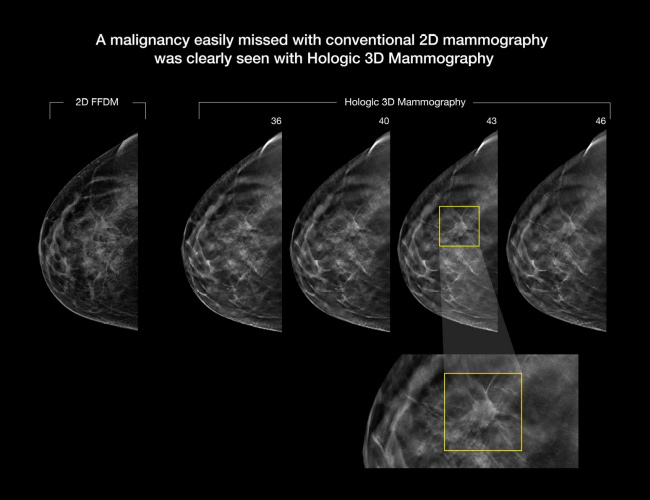

Konvansiyonel iki boyutlu mamografi sistemlerinin temel sınırlılıklarından biri projeksiyon görüntüleme yöntemi olmasıdır. Projeksiyon yönteminde lezyonların / dokuların üst üste görüntüsünün oluşması (süperpozisyonu) nedeniyle lezyon parankim dokusu içinde gizlenebilmektedir.

Lezyonun kontrastı nedeniyle saptanabilir olduğu durumlarda dahi kontur özelliğinin değerlendirilmesi güç olabilmektedir. 3D Tomosentez Mamografi objelerin farklı açılardan projeksiyon görüntülerinin elde edilmesi esasına dayanmaktadır.